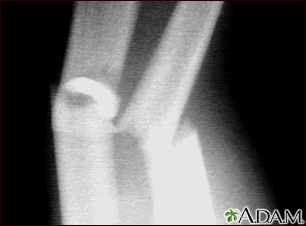

Fracture, forearm - x-ray